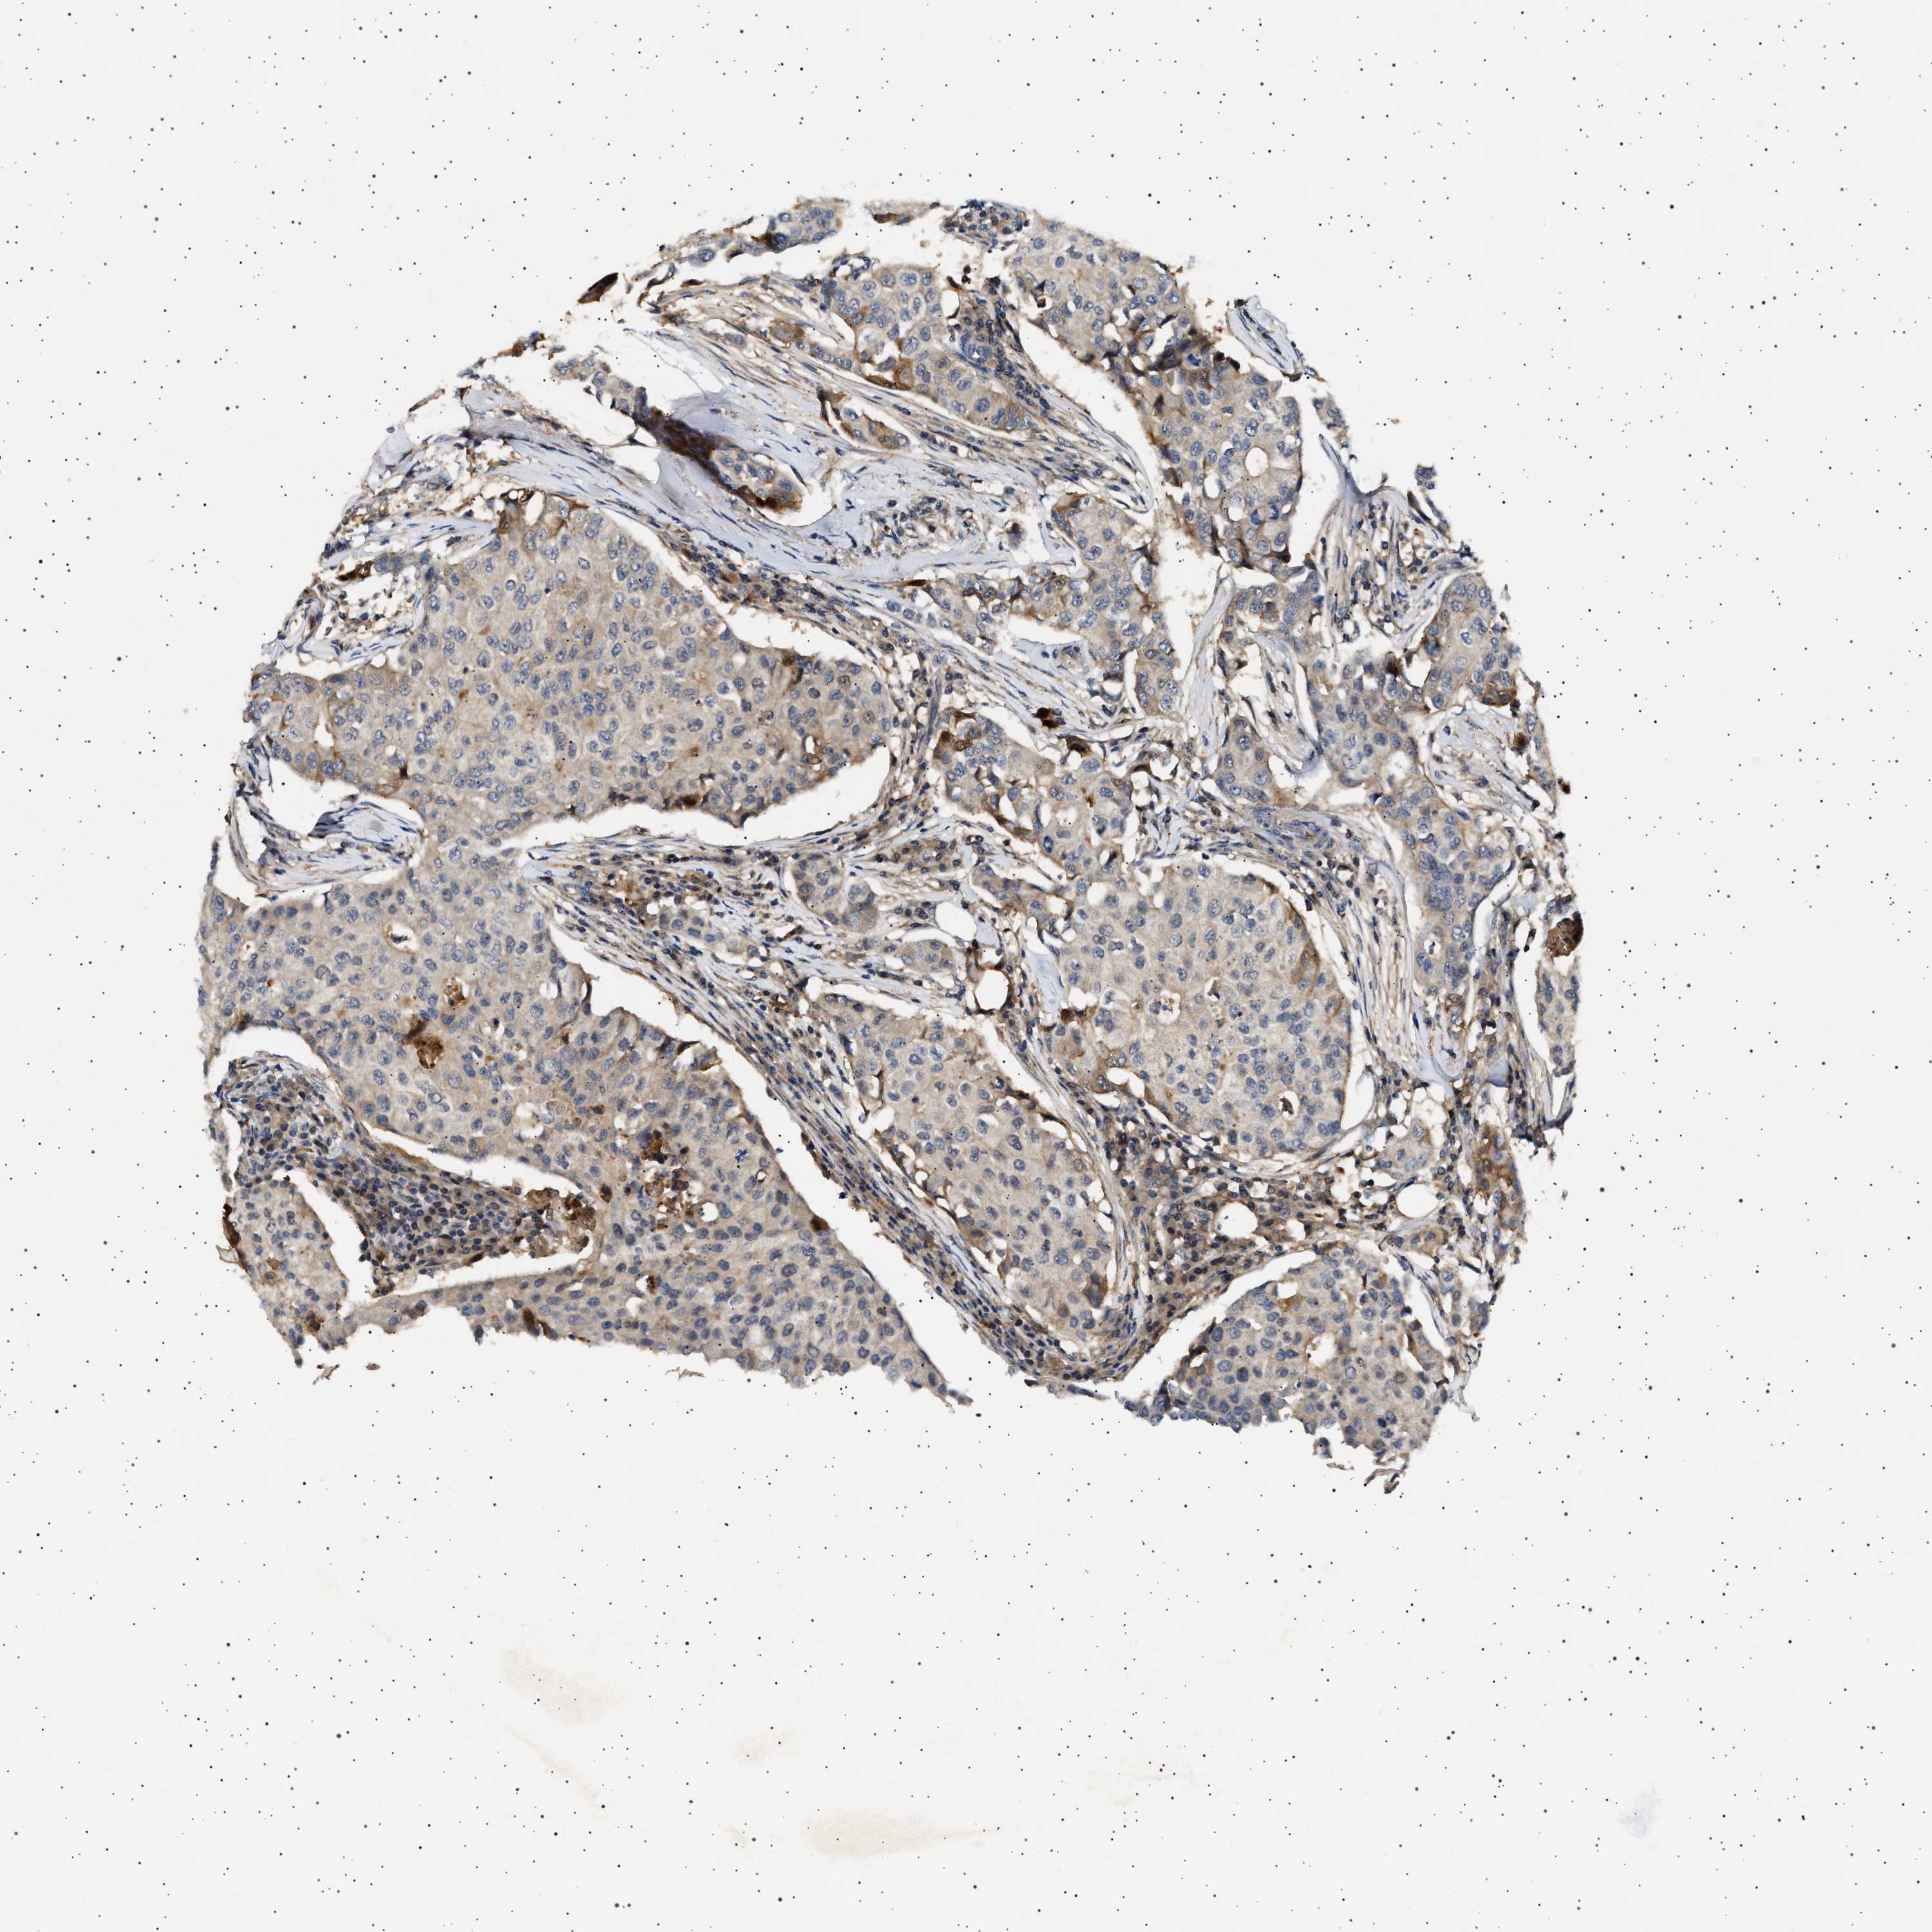

CANCER BREAST CANCER Show tissue menu

BRCA TCGA BRCA VALIDATION PROTEIN EXPRESSION